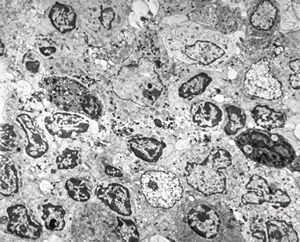

normal mucosa - stomach - parietal cell